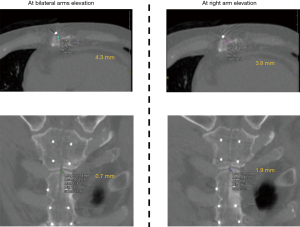

Sternal deviation was examined with computed tomography (CT) (1 mm thickness) approximately 3 weeks after surgery as we usually take a CT scan for patients who underwent a typical aortic surgery at this timing. CT was conducted with two different postures: right upper limb elevation and bilateral upper limbs elevation, in order to evaluate sternal gaps with multi-planar reconstruction using Aquarius Net Station (TeraRecon Inc., Foster City, CA, USA) by radiologists who were blinded to the patients’ backgrounds and group. These two postures can generate different directions of shear stress on the sternum; the bilateral arms elevation yields rostral traction on both the divided sternums, whereas the right arm elevation induces rostral traction only on the right divided sternum. Anterior-posterior gap was defined as the maximal difference in the anterior surfaces between the right and left divided sternum; cranial-caudal gap, as the maximal difference at the top of the manubrium or body between the right and left divided sternum (Figure 2). Absolute values of differences in sternal gaps between the aforementioned two postures were calculated as an indicator of sternal stability since the direction of sternal deviation, if exists, should differ among patients. All clinical information was procured prospectively. Pain on the chest was evaluated by a physical therapist after 10–14 days from the index operation. The level of pain was assessed at three postures, including bed rest, right upper limb elevation, and sit up position (Figure 3), and expressed according to numerical rating scale (NRS), where 0 means no pain, 1–3 means mild pain [nagging, annoying, slightly interfering with activities of daily living (ADLs)], 4–6 means moderate pain (significantly interferes with ADLs), and 7–10 means severe pain (disabling or unable to perform ADLs) (19).